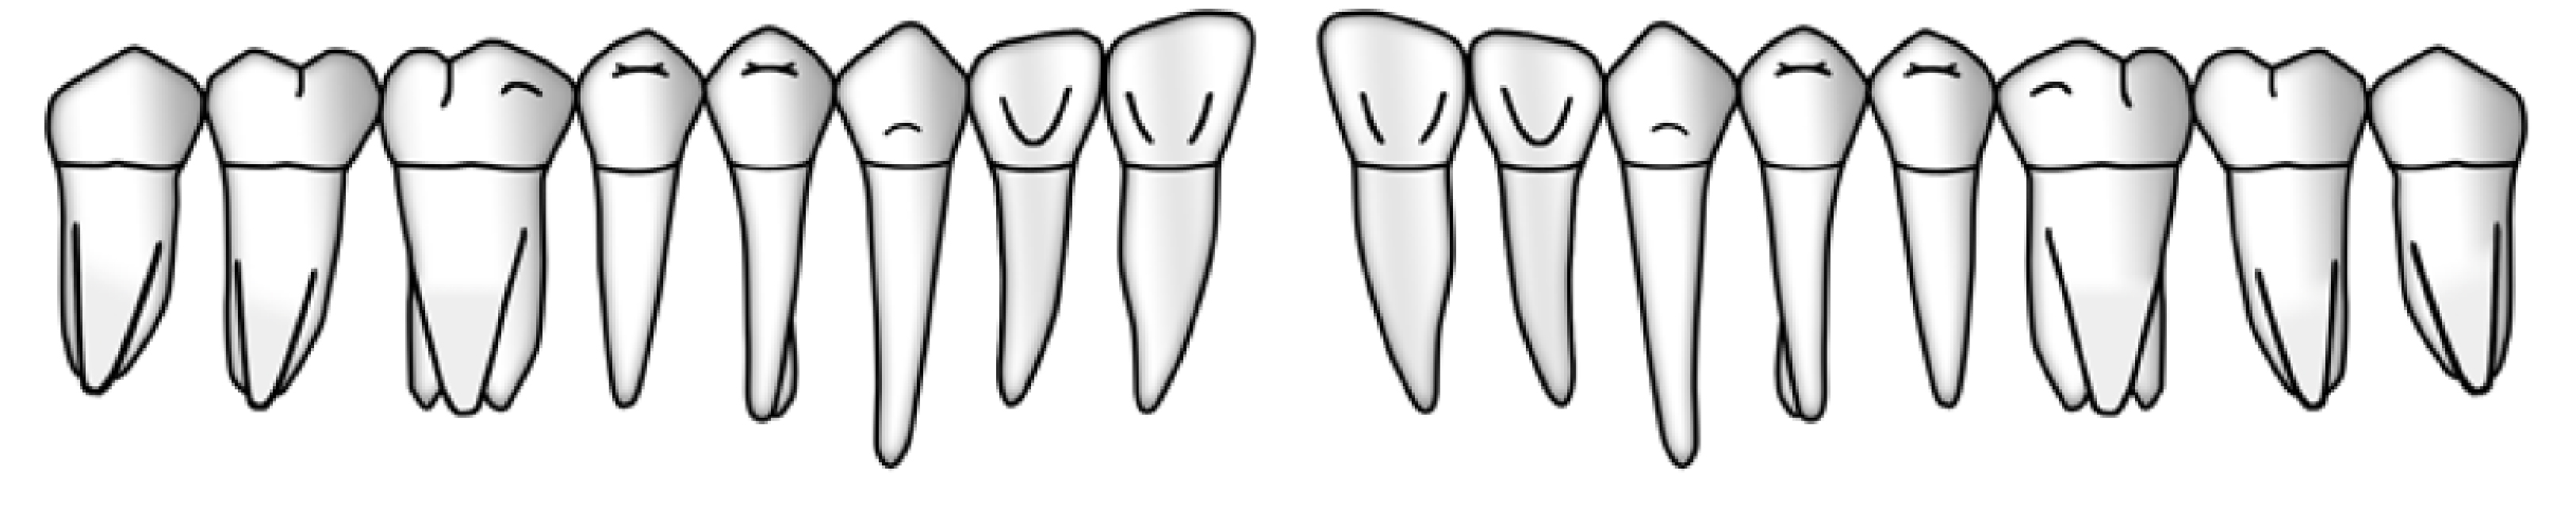

Sechs Messstellen pro Zahn oder Implantat

Entscheidend für die Aufzeichnung sämtlicher parodontalen oder periimplantären Messungen ist die Wahl der richtigen sechs Stellen um den Zahn oder um das Implantat. Hierfür wird der Zahn oder das Implantat von okklusal betrachtet in seinem Umfang in 6 Abschnitte eingeteilt. Für jeden dieser Abschnitte wird die Stelle mit dem höchsten Sondierungswert ermittelt und ausgemessen.

Anstellwinkel der Parodontalsonde

Bei der Messung der Sondierungstiefe wird die Sonde entlang der Zahnoberfläche nach apikal geführt. Dabei kann sie sich in mesio-distaler Achse neigen A resp. B, währenddem die bukko-orale Richtung parallel zur Zahnlängsachse gehalten werden muss.